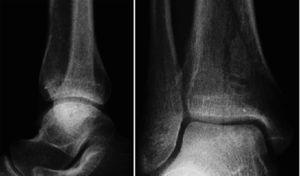

A los seis meses de la cirugía la RMN ya mostraba una buena integración del bloque óseo y del cilindro implantado. Concretamente a nivel de la tibia, no se encontraron edema perifocal, vetas de esclerosis, ni incongruencia de las superficies articulares (fig. 15).

Figura 15